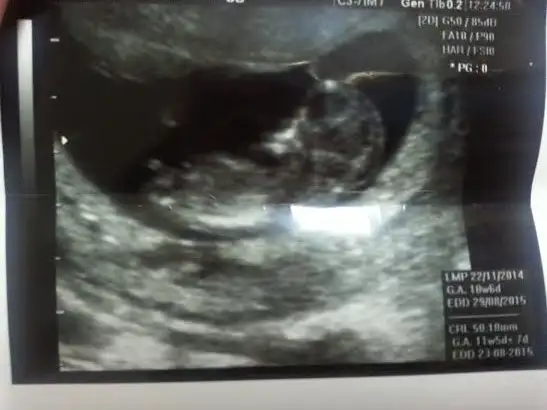

Kızlar 11+4 nolur yorum yapın çok mrk ediyorum

• DSC_0979.webp

DSC_0979.webp

27,9 KB · Görüntüleme: 90